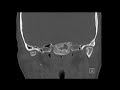

Fibrous Dysplasia Clivus

These images demonstrate a slightly expansile osseous lesion centered in the left aspect clivus with central lucency and peripheral ground glass appearance. The cortex is intact. These findings are characteristic of fibrous dysplasia. It can have a variable appearance which can look misleadingly aggressive on MRI. This is a congenital process where fibrous stroma replaces bone. It is predominantly found in younger patients and can result in deformity. Polyostotic fibrous dysplasia is a feature of McCune Albright syndrome. No treatment is necessary if the patient is asymptomatic.